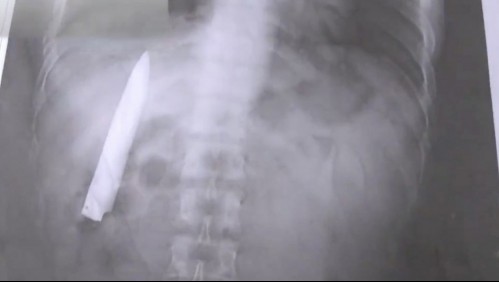

Mundo "Siempre sentía dolor": Fue apuñalado hace 14 meses y aún tenía la hoja del cuchillo en su torso